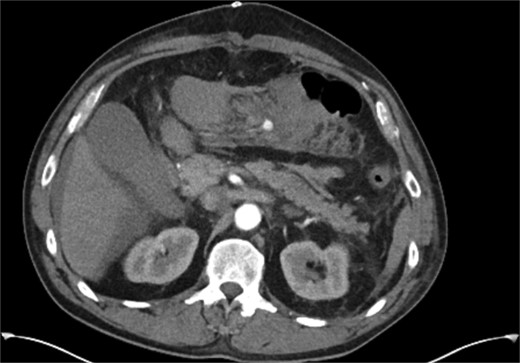

On day five post-operatively, the patient deteriorated, developing hypotension, diaphoresis, a new oxygen requirement, and complaining of new onset back pain. This is in conjunction with a drop in haemoglobin (Hb) from 129 g/L (day one post-operatively) to 89 g/L on Day 5. An abdominal CT Angiogram was performed, showing a pseudoaneurysm of the Marginal artery of Drummond measuring 1.2 × 1 × 1 cm (AP × TR × CC) with some surrounding haematoma in the small bowel mesentery (see Fig. 1). Following multi-disciplinary team (MDT) discussion, three possible management options arose: observe and re-scan the following day and optimize Hb, embolize the artery (although this has a risk of bowel infarction) or to resect the bowel. We decided to adopt a watch-and-wait approach and repeat the CTA the following day, which showed no significant change in the pseudoaneurysm. He was discharged home on Day 6 post-operatively.

CT angiogram performed on 5th postoperative day, demonstrating a small false aneurysm (1.2 × 1 × 1 cm) arising from the marginal artery of Drummond.